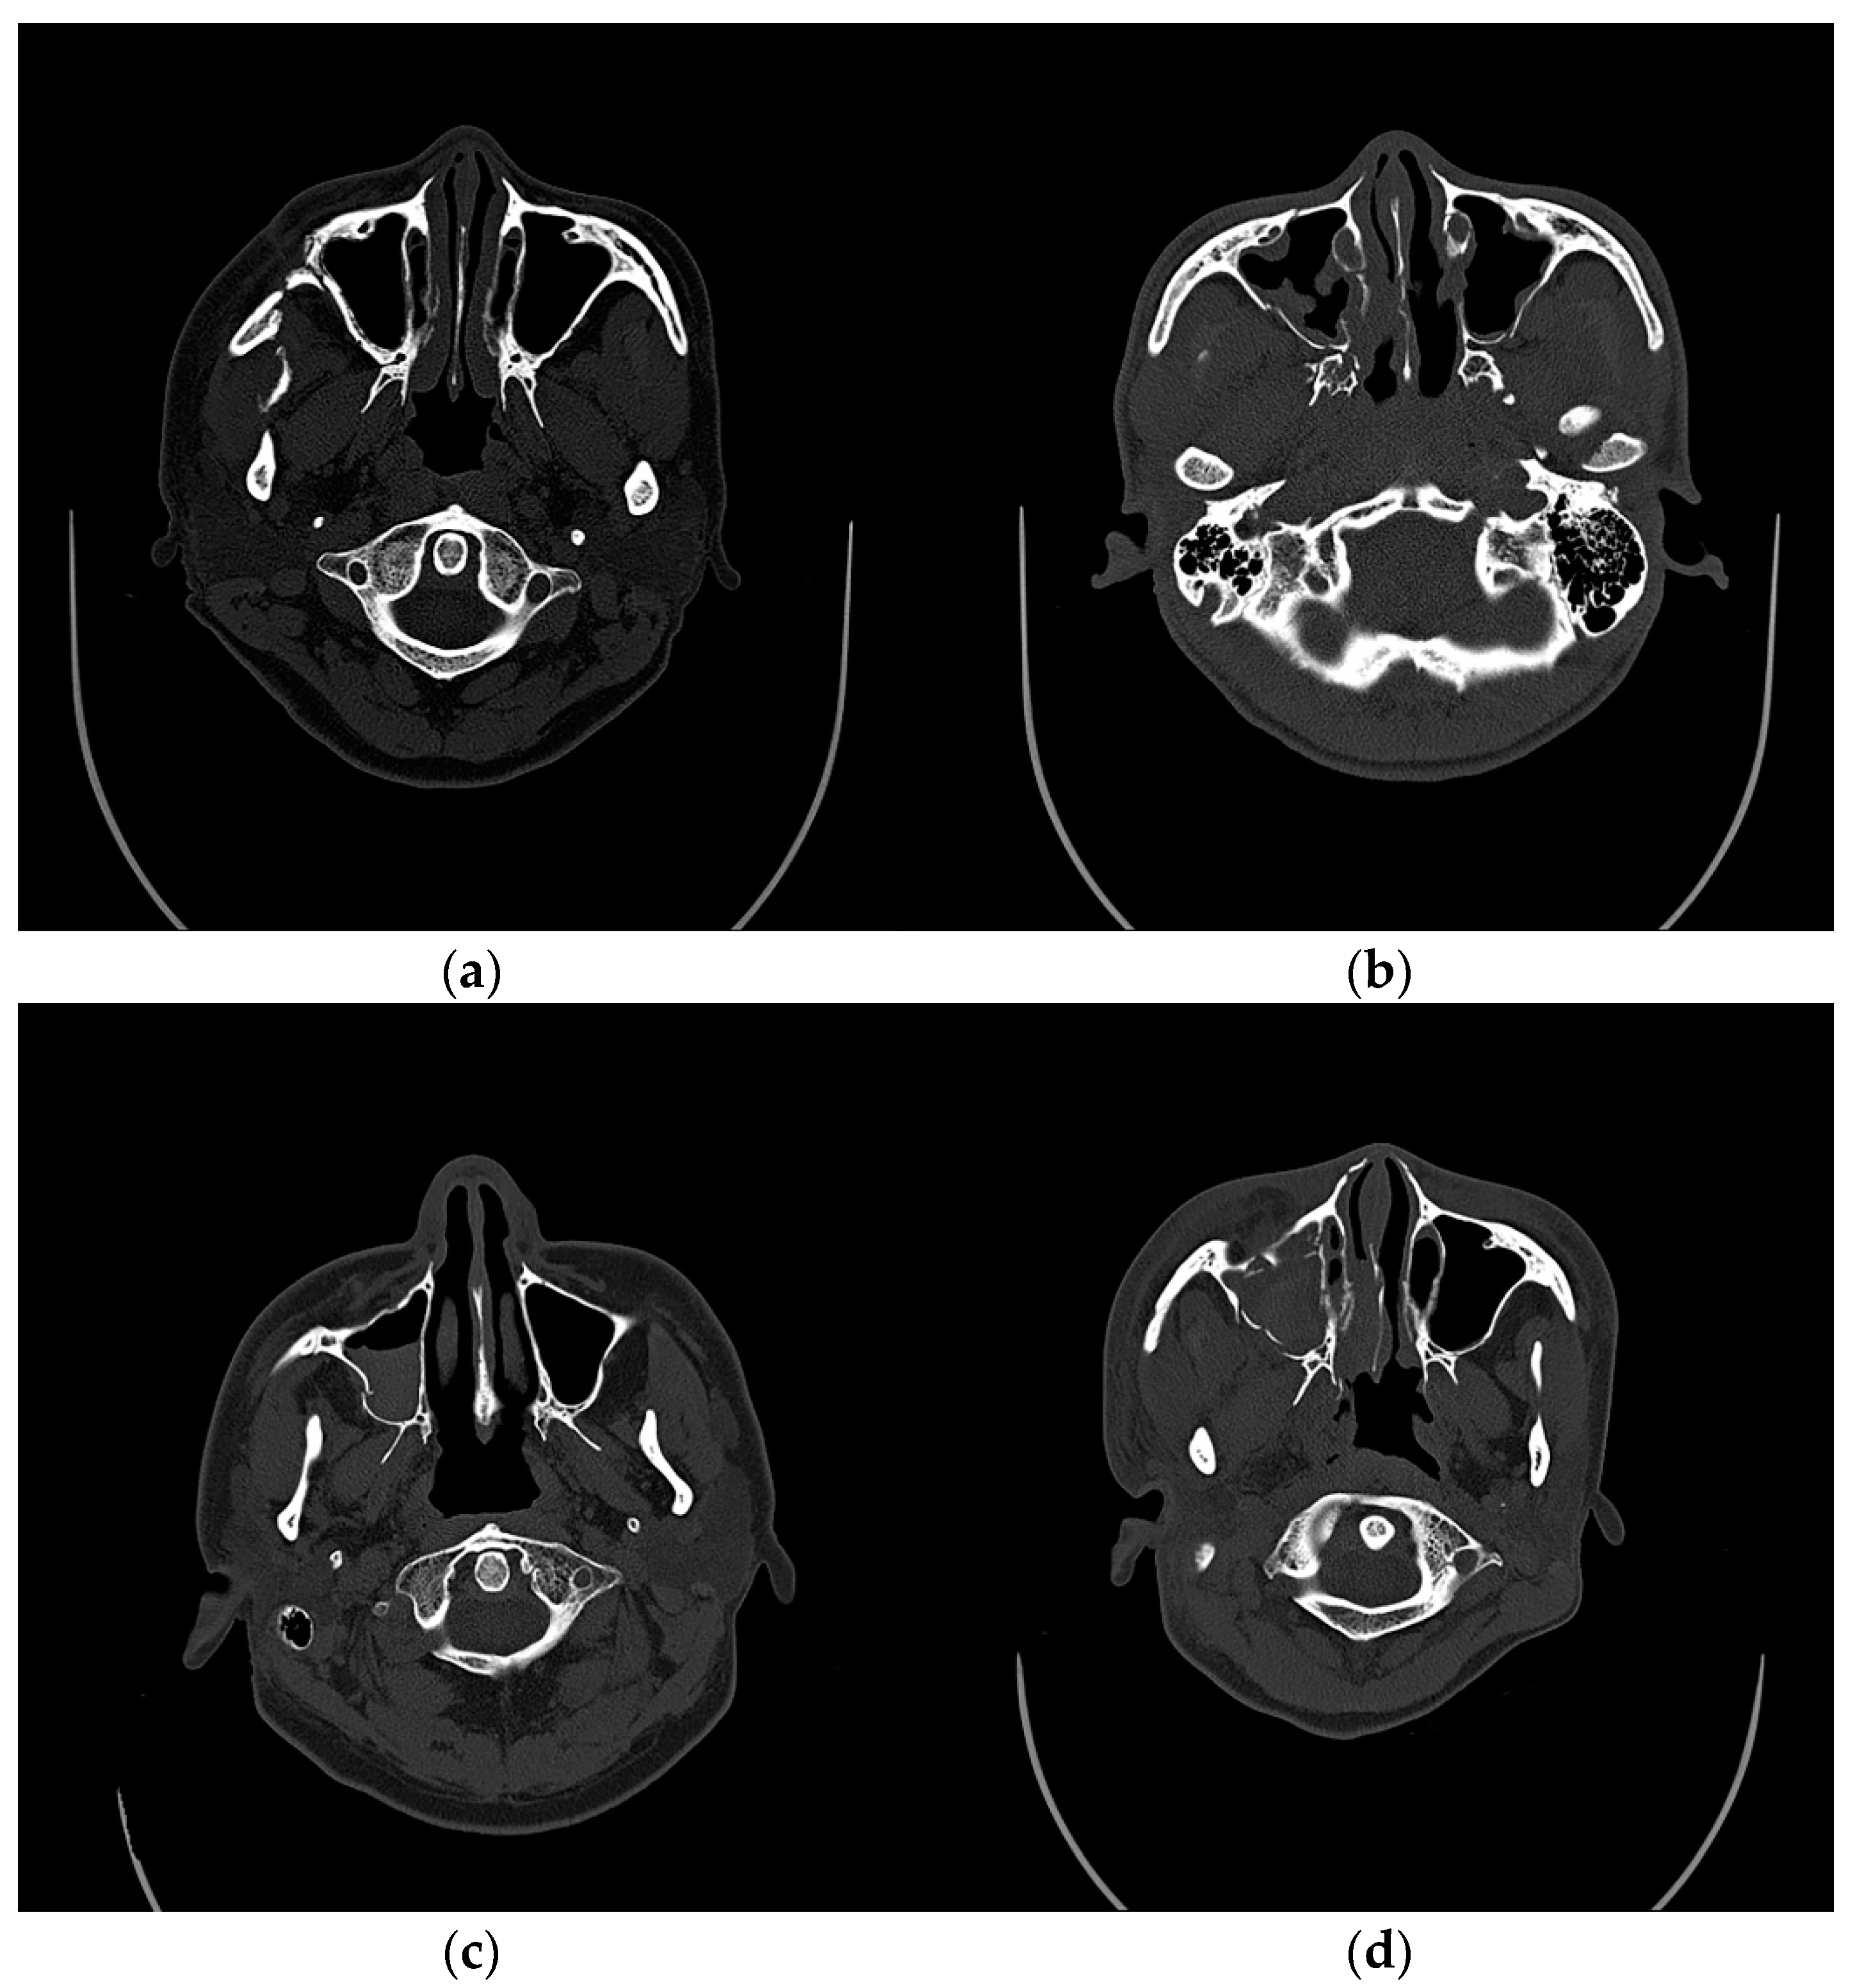

Preoperative CT evaluations of the maxillary sinus were classified as normal, mucosal thickening, gas–fluid level, and total opacification based on Rouby’s classification and Gliklich Metson’s classification (Figure 1) [22,23,24]. As for the mucosa thickening, the author used the criterion of Sanchez-Perez et al., in which the thickening of the mucosa from 2 mm was considered pathological [27]. This was considered only when the mucosa thickening location was not related to obvious dental lesions. The presence of gas–fluid in the sinus was evaluated based on the presence of a fluid opacification, noted on the CT axial scan image, according to the criterion of Bomeli [28]. The presence of total opacification in the sinus was noted on the CT axial, sagittal, and coronal scan images.

Figure 1.

Representative CT sections showing the different preoperative evaluations of the maxillary sinus. (a) normal; (b) maxillary mucosal thickening; (c) gas–fluid level; (d) total opacification.